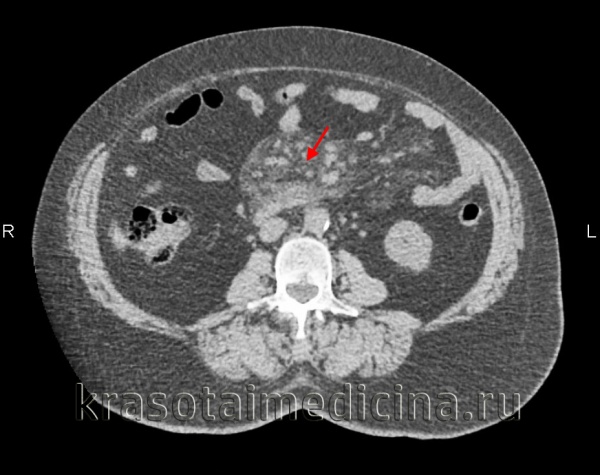

(Слева) На аксиальной КТ у пациента с болевой симптоматикой и лихорадкой определяется инфильтрация брыжейки тощей кишки, отграниченная псевдокапсулой. Визуализируются также множественные хорошо заметные брыжеечные лимфатические узлы с жировым «гало». При ПЭТ не было выявлено гиперфиксации радиофармпрепарата, симптомы регрессировали после назначения стероидной терапии.

(Справа) При аксиальной нативной КТ у пациента с длительно существующим болевым синдромом выявлена инфильтрация брыжейки тощей кишки с псевдокапсулой. Брыжеечные сосуды сдавлены, но без признаков обструкции. Все эти изменения являются проявлением и склерозирующего мезентерита.

(Слева) На аксиальной КТ с контрастным усилением определяется объемное образование брыжейки инфильтративного характера, вовлекающее брыжеечные сосуды. Обратите внимание на застойные изменения брыжеечных вен. Все это признаки склерозирующего мезентерита.

(Справа) На аксиальной КТ с контрастом у пожилой женщины с болевой симптоматикой и диареей определяется мягкотканное объемное образование в основании брыжейки тонкой кишки, окружающее и сдавливающее брыжеечные сосуды. После биопсии был подтвержден диагноз фиброзирующего мезентерита.

КТ органов брюшной полости. Увеличение размеров и количества лимфоузлов в корне брыжейки тонкой кишки на фоне выраженного ее уплотнения